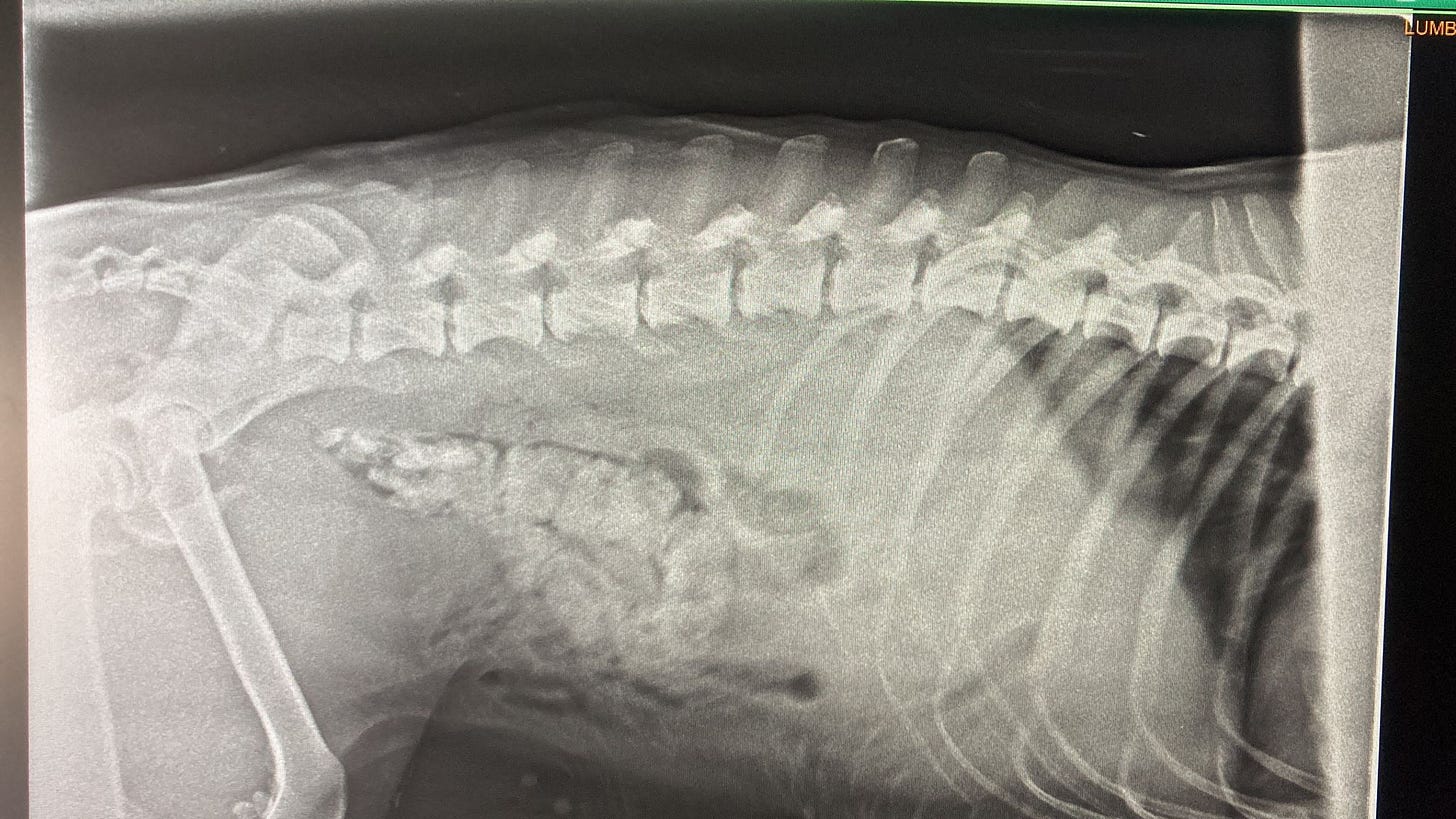

Adam’s tests revealed that he had fractures in the pelvic area & a nasty infection. The infection most likely occurring before the accident.

He also had problems emptying his bladder & bowel. His spine was undamaged so it wasn’t a spinal injury causing this. Sometimes a bullet (yes, our dogs get shot a lot) can be found near the spine which causes these kind of problems but that wasn’t the case with Adam either.